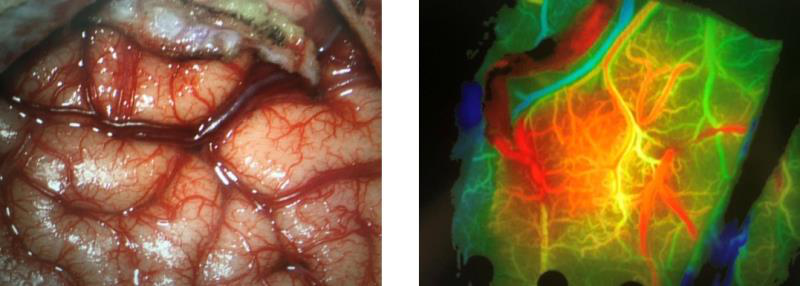

与其他可用于深部动脉瘤治疗的微创方法相比,endoport辅助显微外科具有一定的优势。首先,endoport的优势是微创:皮层造瘘中,endoport的光面结构能有效地减少造瘘通道皮层的挫伤,从而减少了对脑组织的继发损伤。其次皮层造瘘口稳定,减少了人为使用脑压板过程中造成的造瘘口撕裂。然而endoport也存在相应弊端[7],钙化病变和直径大于3厘米的病变可能难以通过endoport切除。

在本例病例中,针对脑室内动脉瘤,我们首选血管内治疗栓塞脑室旁动脉瘤,因为血管过于迂曲尝试失败。术后出现脑室内出血,于是启动备选方案,急诊在磁共振导航下通过endoport辅助进行动脉瘤切除,同时部分清除脑室内血肿并放置脑室外引流,降低远期脑脑积水的风险。随着神经内镜的普及,深部的脑血管病变的治疗方案有了更多的选择,而充分的术前评估与周全的手术方案规划是手术安全与成功的基石。